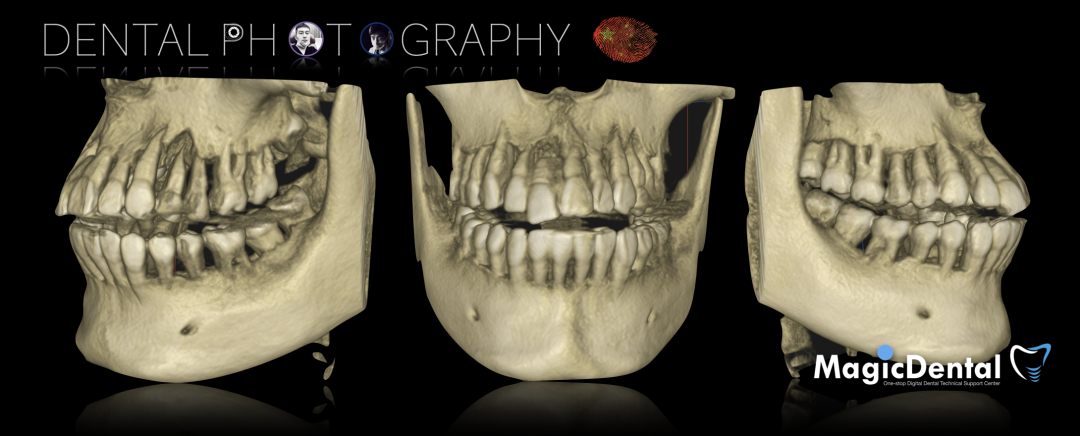

CBCT显示全口牙槽骨水平吸收严重,下颌骨量保存大于上颌

术后三个月复查CBCT

采用ICAM4D重新进行上颌数字化印模,并利用即刻修复体进行面弓转移。